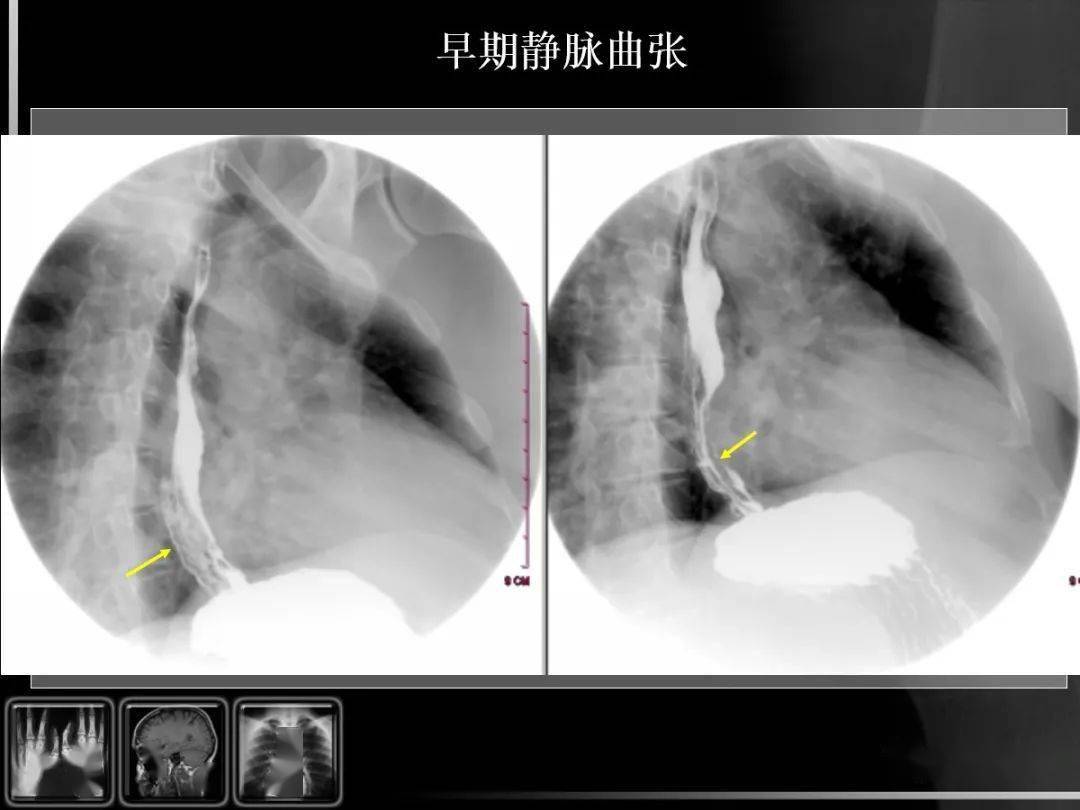

消化道疾病影像诊断与鉴别_造影

图片尺寸1080x810